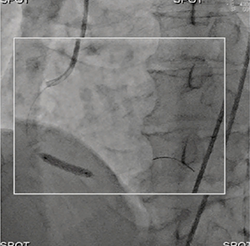

術者は手技中に,透視画面中の一部分(関心領域)を集中して見ていることが多い。また,関心領域以外の周辺部は,全体における位置関係や拡大率の情報を与えてくれるものである。DoseRite SpotFluoroは,その術者特性を考慮することで開発された機能である。

これは,X線絞りを利用し,設定した関心領域にのみX線を照射し,患者に照射される面積線量を低減するとともに,患者や寝台などにX線が跳ね返ることで発生する散乱線を減少させるため,術者被ばくの低減を可能とする機能である。X線照射範囲外の領域には,直前の最終透視画像を静止画で表示することで,真っ暗にならず,位置関係や拡大率など手技に必要な情報を消失させない工夫を施した。本機能を活用することで,患者はもちろん術者をはじめとするカテ室内に従事するすべてのスタッフの被ばくも低減でき,医療従事者への安全を提供している(図2)。

図2 DoseRite SpotFluoroの活用例

照射範囲内(□)にのみX線を照射し,照射範囲外は直前の最終透視像を静止画で残すことで,位置情報を確保している。